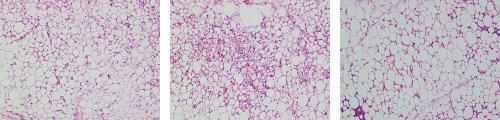

Adipozyten bestehen aus Fetttröpfchen, das als Fettgewebe bezeichnet wird und in zwei Arten klassifiziert werden kann: weißes Fettgewebe (WAT) und braunes Fettgewebe (BAT). Jede Zelle des weißen Fettgewebes enthält ein einziges großes Fetttröpfchen, das Fett speichert. Braune Fettgewebezellen enthalten zahlreiche kleinere Tröpfchen. Diese Zellen verbrennen Fett, um Wärme zu erzeugen.

Wenn weißes Fettgewebe, aufgrund von Fettleibigkeit, wächst, führt das zu einer Dysfunktionalität der Adipozyten, welche wiederrum einige Krankheiten begünstigen kann.

- Menge

- 1955 Zellen

- Durchschnittsfläche

- 122 µm2

- Standardflächenabweichung

- 352 µm2

- 3162 Zellen

- 68 µm2

- 186 µm2